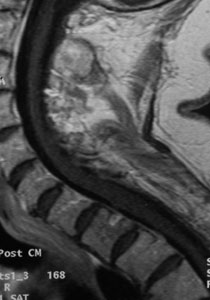

67歲女性患者,在T1/2椎管水平被診斷出患有腦膜瘤。主訴雙下肢感覺異常和逐漸加重的步態(tài)不穩(wěn)。

磁共振成像顯示,有一個明顯增強的腫瘤(由箭頭標出),它幾乎完全占據(jù)了脊髓的管腔空間。

在脊髓管腔邊緣,可以看到灰色的鐮刀形結構(位于箭頭所指區(qū)域),代表剩余的脊髓組織。

術后MRI掃描顯示腫瘤已被完全移除,患者脊髓的壓力得到了有效緩解。

雖然患者長期受病情困擾,感覺功能障礙的改善有限,但積極的方面是,他的姿勢控制能力有了顯著進步,這降低了日?;顒又幸蚱胶鈫栴}帶來的風險,并提高了他的自理能力。